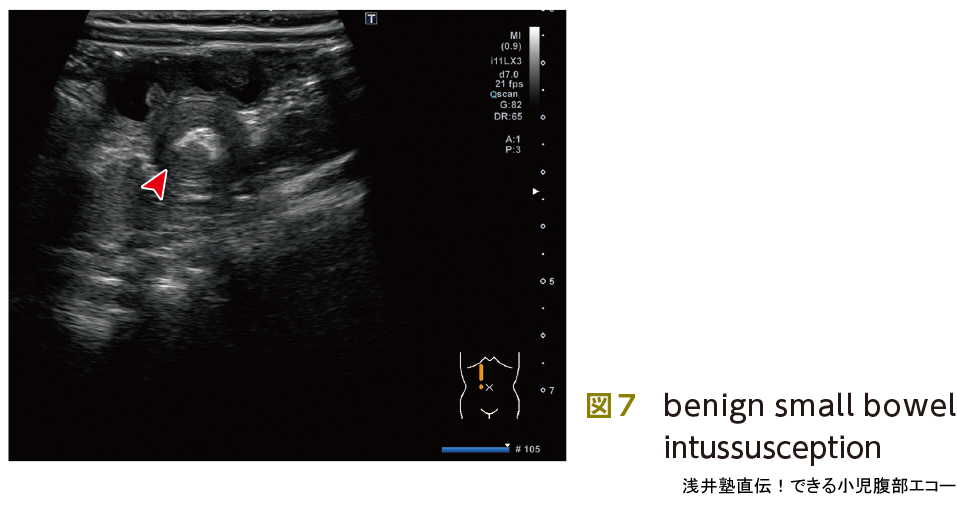

最後に紛らわしいもの,経過観察でいいもの(いわゆる,もどき)をピットフォールで記載いたしますので参照下さい(図6,7,ピットフォール②).

図7も腸重積症として整復術を予定されていた症例です.こちらも経過観察としました.benign small bowel intussusceptionともよばれ小腸と小腸が重なっているだけの所見と考えられており,無症状なら基本的に経過観察です.

- ① 外筒が2.5 cm以下

- ② 重積腸管の長さが3 cm以下

- ③ 重積腸管の蠕動がみられる

- ④ 特異的な先進部が欠如